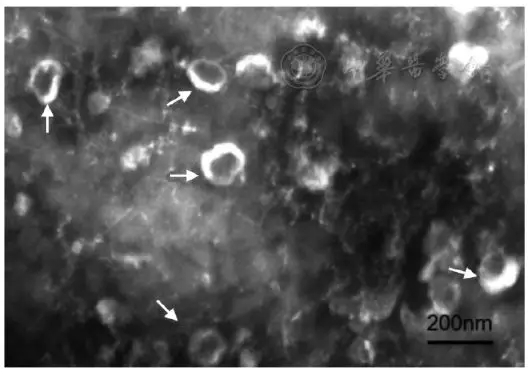

透射電鏡下觀察,外泌體提取物均呈圓形或類圓形的小囊泡,直徑約40~100 nm,包膜完整,背景清晰,未見細(xì)胞碎片,如圖1。

圖1人血清外泌體透射電鏡觀察圖,箭頭所示為外泌體(×46 000倍)

圖1顯示透射電鏡下觀察,外泌體呈圓形或橢圓形,包膜完整,背景清晰。Zetaview可視化納米粒度儀檢測(cè)結(jié)直腸癌患者外泌體直徑主要集中在40~160 nm,最大分布峰值為99.5nm,占比98.4%,濃度為3.3×1012個(gè)/ml,高于文獻(xiàn)報(bào)道[8,9,10]。雖然外泌體所含成分根據(jù)細(xì)胞及組織來源不同而有差異,但所有的外泌體都包含膜轉(zhuǎn)運(yùn)蛋白和膜融合蛋白(GTPases、Annexins和Flotillin等)、熱休克蛋白(HSP70、HSP90等)、四跨膜蛋白(CD9、CD63、CD81和CD82等)、參與多囊泡體生物合成的蛋白質(zhì)(Alix和TSG101等) 以及脂質(zhì)相關(guān)蛋白等[11]。本研究選用熱休克蛋白(heat shock proteins,HSP)和四跨膜蛋白CD63作為血清外泌體的鑒定指標(biāo),我們通過western Blot檢測(cè)到了外泌體中這兩種蛋白質(zhì)的存在,同時(shí)也印證了ExoQuick試劑盒抽提血清外泌體方法的可行性。